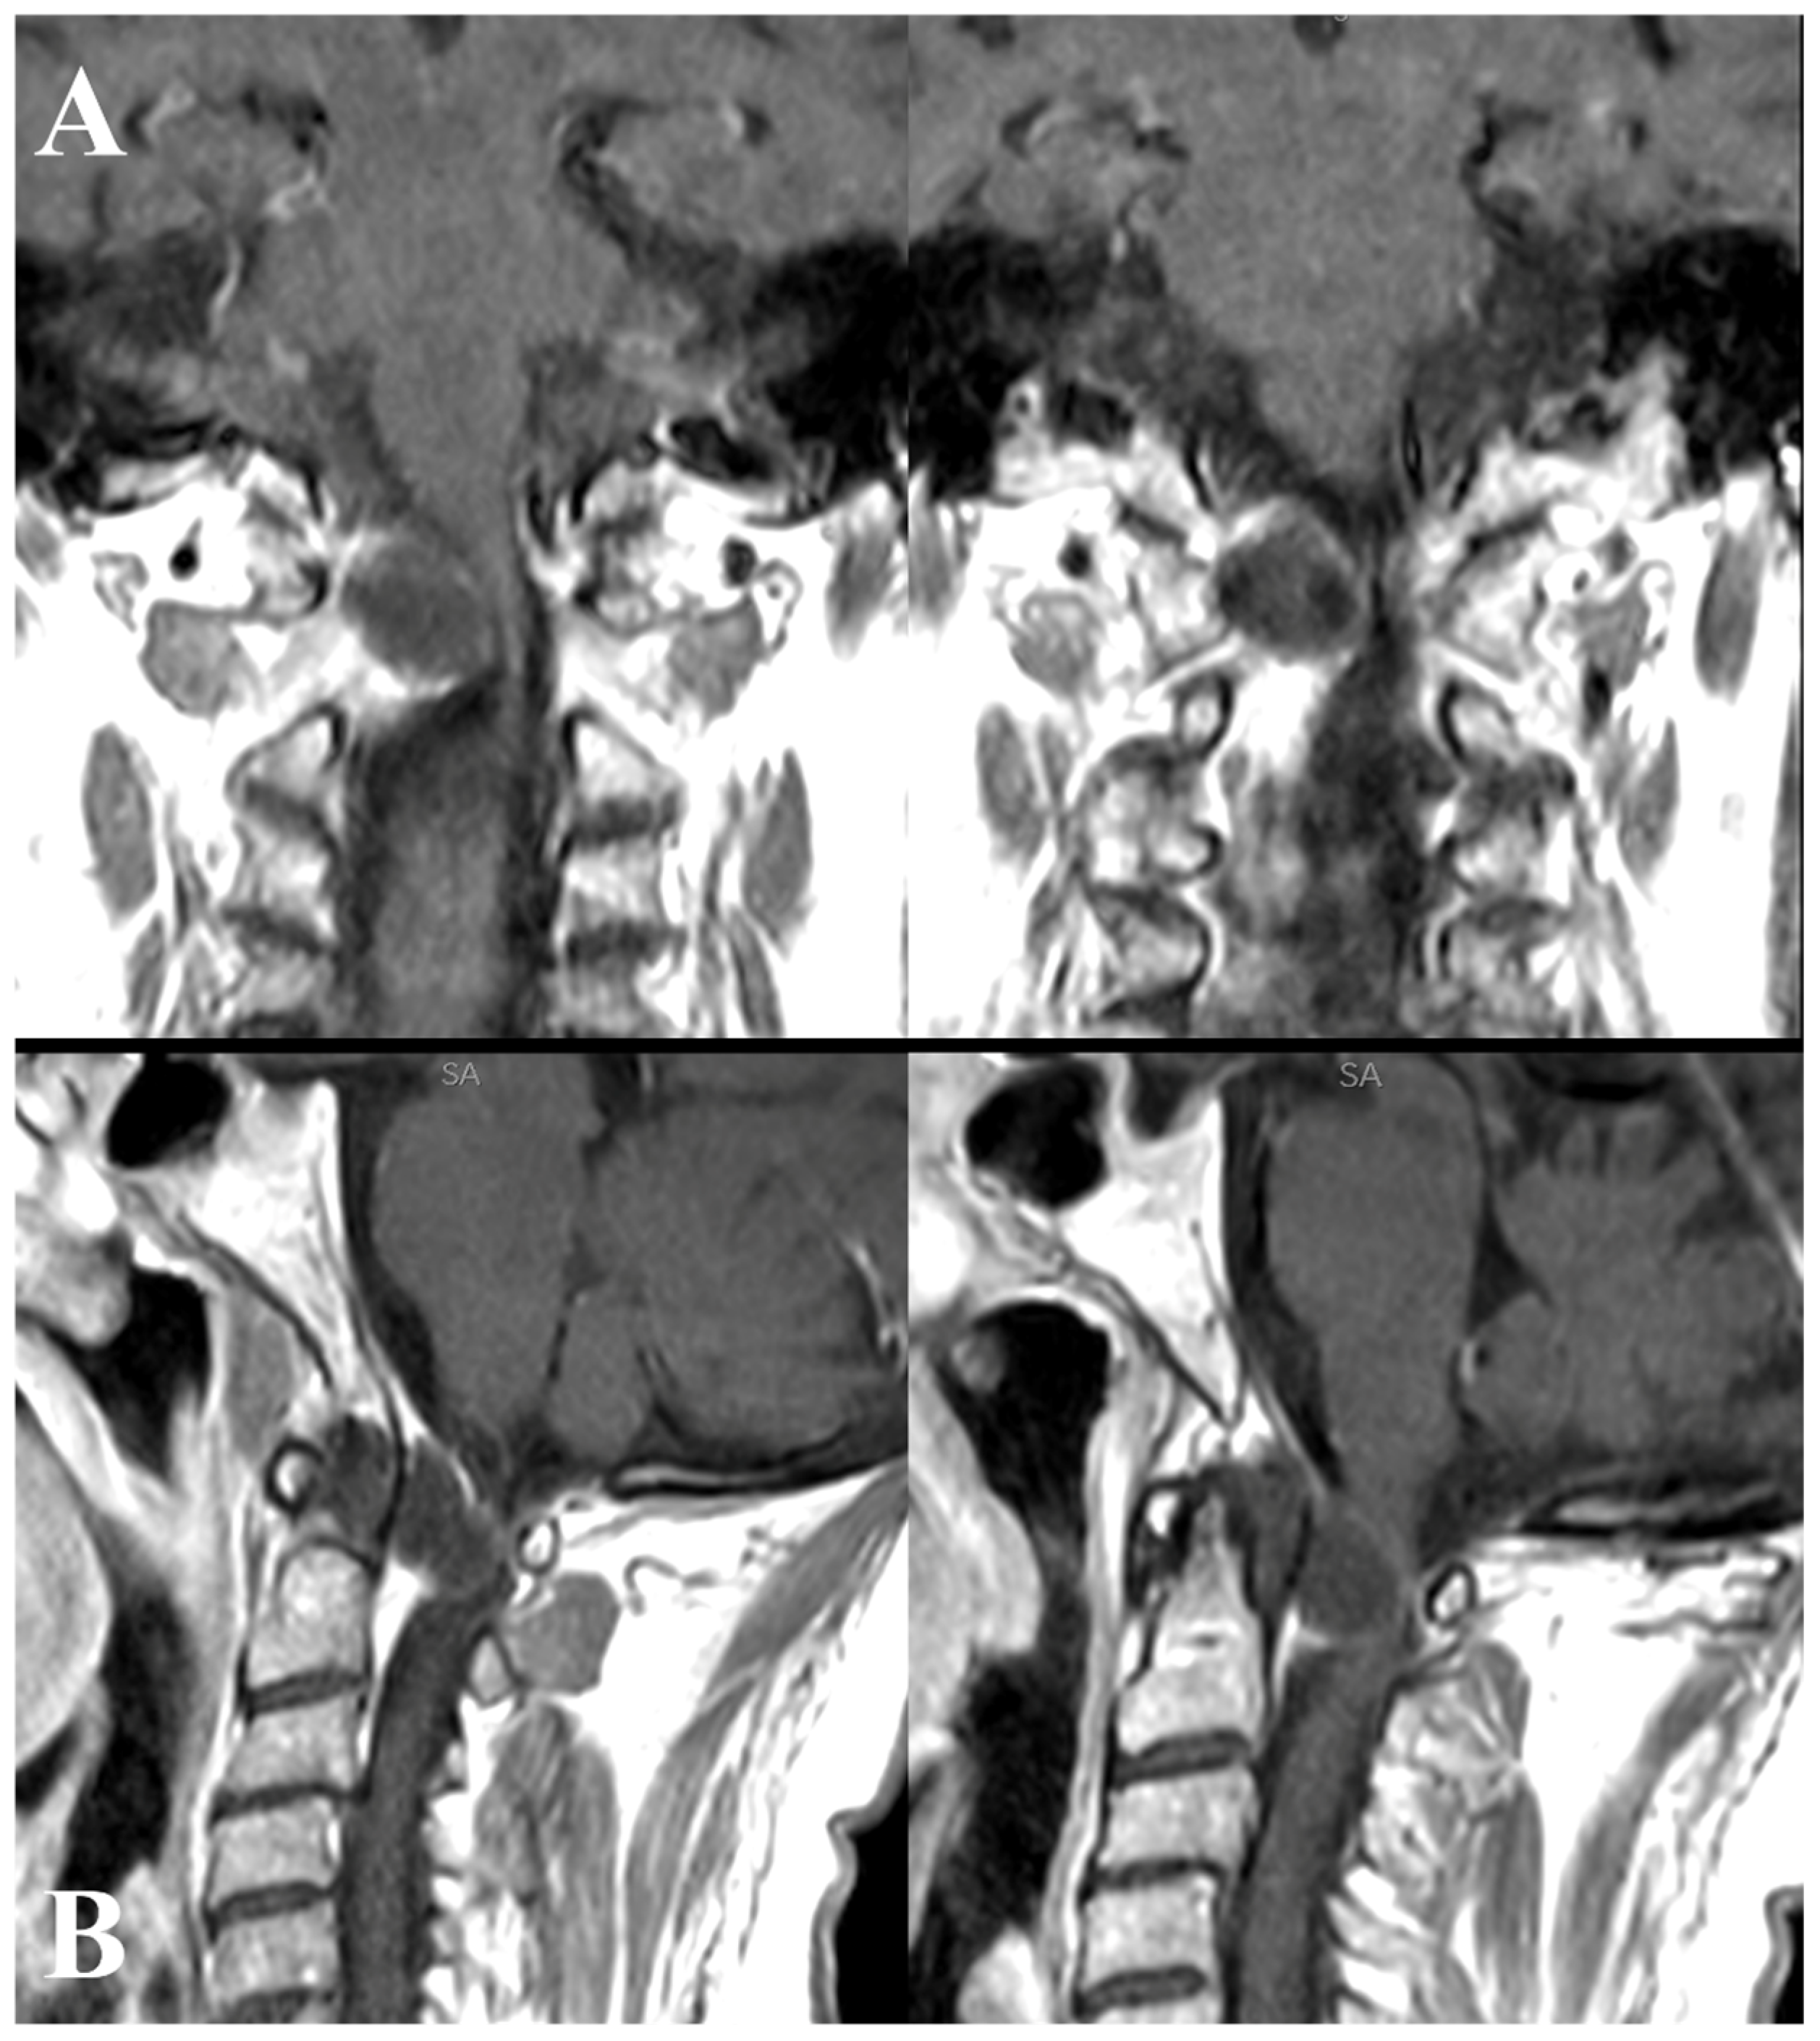

A 56-year-old woman was admitted to our institution due to a sudden onset of right hemiparesis following three days of neck pain. Upon examination, she exhibited hemi-hyposthenia (BMRC 3/5), inability to stand or walk, heightened deep tendon reflexes bilaterally (particularly on the right side), and bladder dysfunction. Additionally, she displayed nuchal rigidity and positive Kernig and Brudzinski signs. Initial hematological and coagulation tests yielded unremarkable results, and the patient had no history of vertebral trauma. Considering the abrupt symptom onset, suspicions arose regarding either a malignancy or hemorrhage from a vascular malformation. Given the concurrent presence of meningeal signs, emergency computed tomographic (CT) scanning from the brain down to the craniovertebral junction (CVJ) was conducted. The CT scan revealed an iso-hyperdense lesion at the CVJ. Subsequent T1- and T2-weighted magnetic resonance imaging (MRI) identified a large anterior, right lateral tumor measuring approximately 1.3 × 1.6 cm at the C1–C2 level. The tumor appeared hyperintense in T2WI and hypointense in T1WI, exhibiting ring enhancement after gadolinium administration (Figure 2 and Figure 3).

Figure 3.

T1-weighted magnetic resonance imaging (MRI) coronal (A) and sagittal (B) sequences with gadolinium administration showing the same tumor at the C1–C2 level. The tumor exhibits hypointensity in T1-weighted imaging (T1WI) and displays ring enhancement after gadolinium administration.